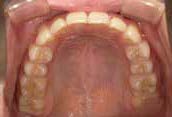

さらに、上からあごの骨を見たところ、中央がくびれた“ひょうたん型”に変形しており、あごの成長にも偏りが見られました。

診断の結果、前歯の中心も少し左にずれており、特に犬歯が生えるスペースが足りない状態でした。